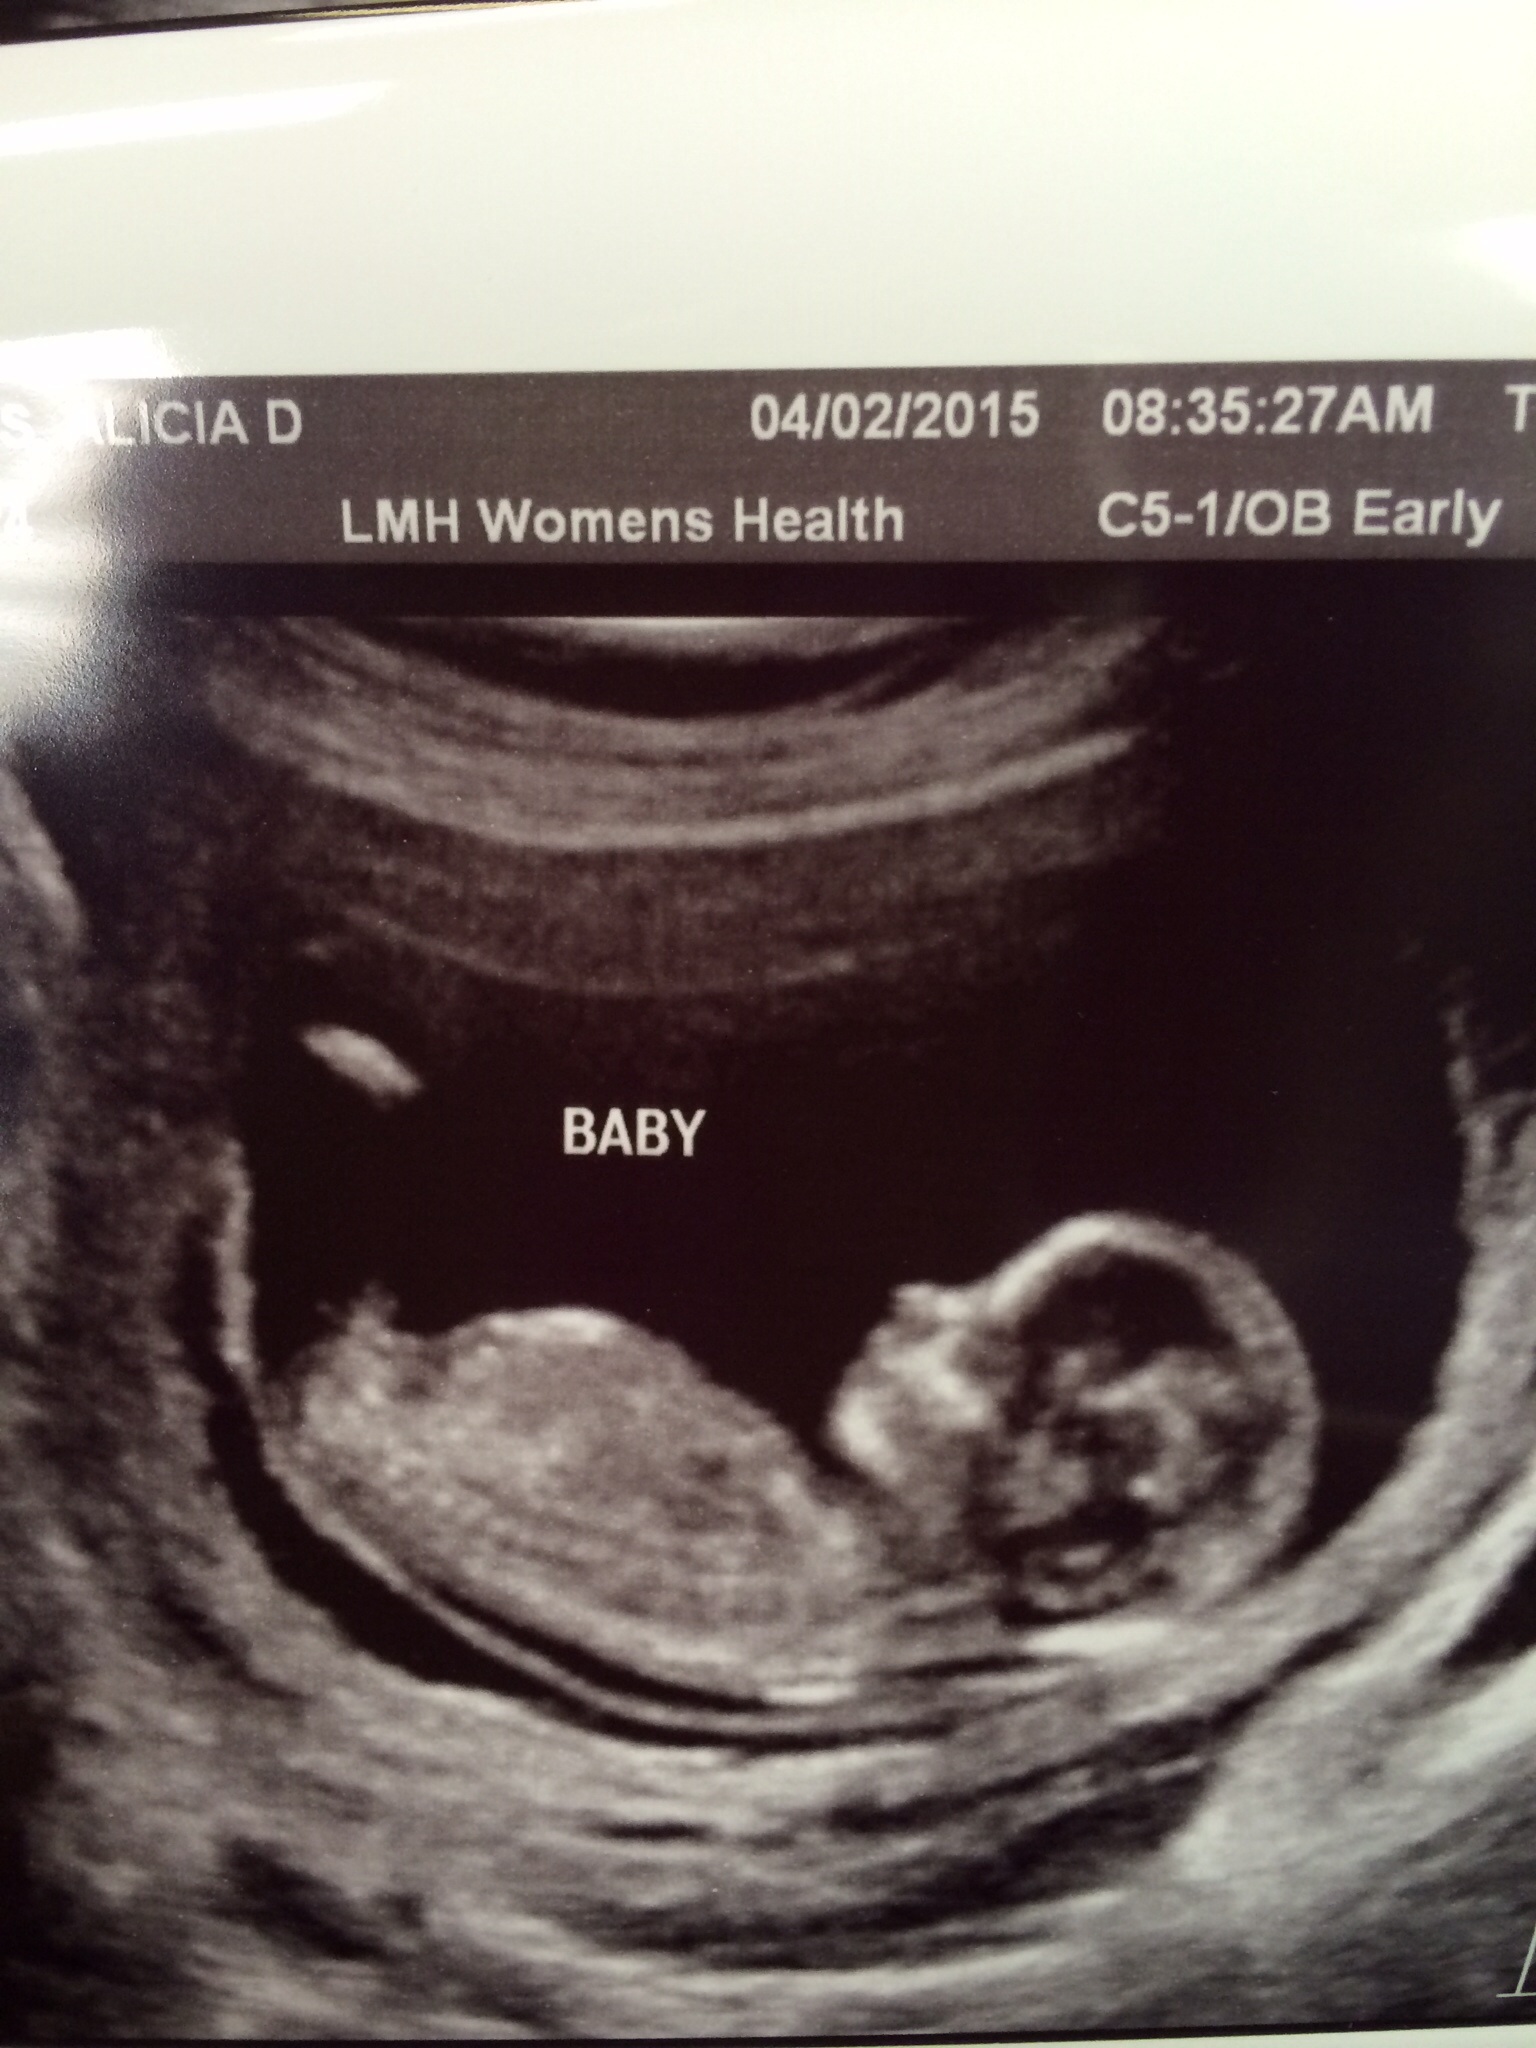

This is the best Nub view I got. I was measuring 13+6. But by my +opk I am more like 13+1.

If the tech would have snapped the shot 1-2 seconds before this one you could see the nub waaay better. It was nice and flat, and there was no shadow above it.

All guesses welcome!!!!! Would really love Nahri's opinion;) Attachment 24581

Oh Queen B that's a lovely round girly skull and flat nub so GIRL from me! The only thing throwing me is the slight shadow....any more pics? Xx

for that gestation I would say girl. The shadow is a throw for sure until you zoom in. You can clearly see the fork and the shadow being part of the leg.